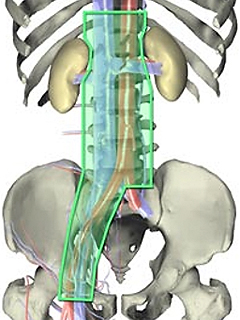

2.後腹膜リンパ節郭清

後腹膜リンパ節とは、お腹の大血管周囲にあるリンパ節です。精巣腫瘍は始めにこのリンパ節に転移を起こすことが多いため、転移のないⅠ期の場合でも、再発を防ぐ目的でこの部分のリンパ節とその周りの組織を取り去る手術が行われることがあります。

最初から後腹膜リンパ節に転移がある場合、化学療法によってがん細胞を十分に死滅させ、腫瘍マーカーが正常となってからこの手術を実施します。

後腹膜リンパ節郭清の範囲

(右精巣腫瘍の場合)